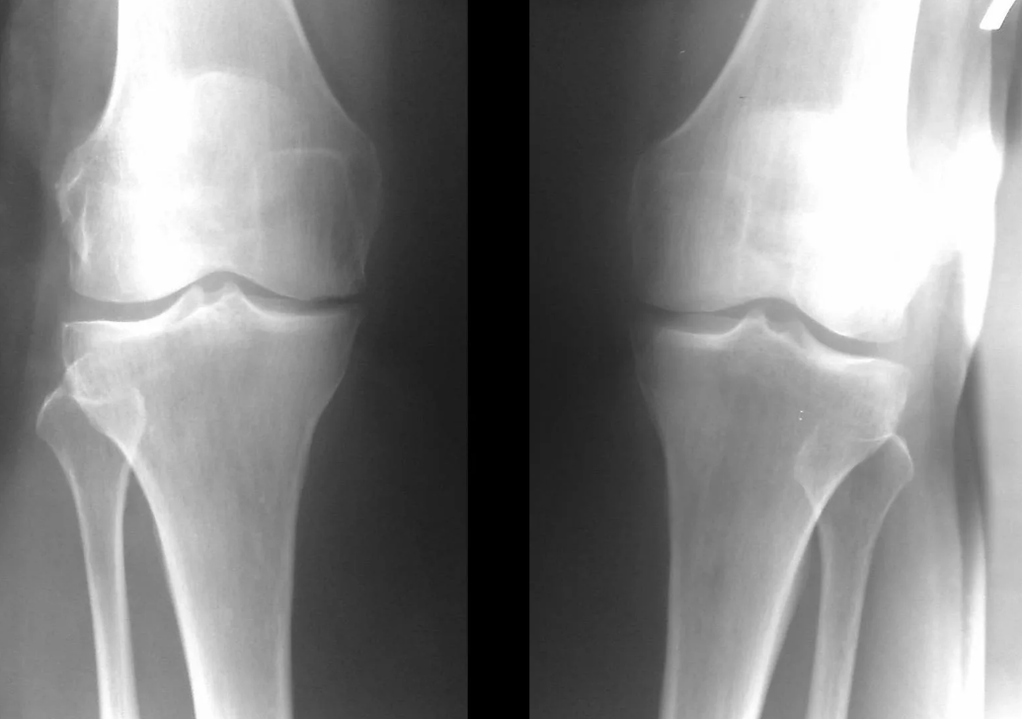

Instrumental diagnosis of arthrosis of the knee joint

In the vast majority of cases, it is sufficient to examine and x-ray the knee joint in two views (direct and lateral).Clinical data and images help determine the stage of the disease.

In the initial stages of the disease, with minor changes in the bone tissue, the X-ray examination is not so valuable.At this stage, gonarthrosis can be diagnosed by arthroscopy.The accuracy of the method is very high;only its invasive nature and price can stop it.